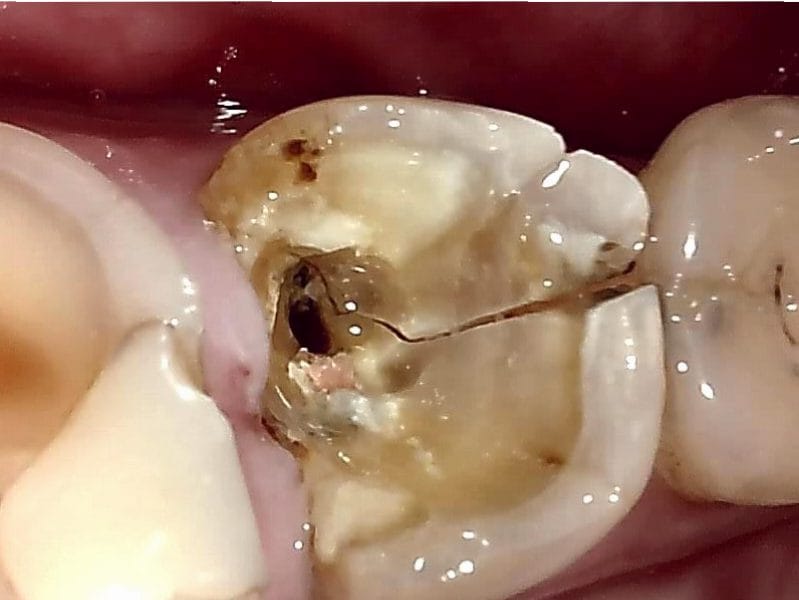

奥歯割れちゃったペポ…

割れる前から駄目だろこれ

上下左右の奥歯がこれ

両隣の歯も終わってない?

中身スカスカ❤️

マジでヤバいだろこれ

ねぇ何でこうなる前に歯医者行かなかったの?

外から見ると小さい虫歯なのに内部に穴が空いてたとかある

パキって割れたと思ったら欠片取れて凹みたいな形になってる